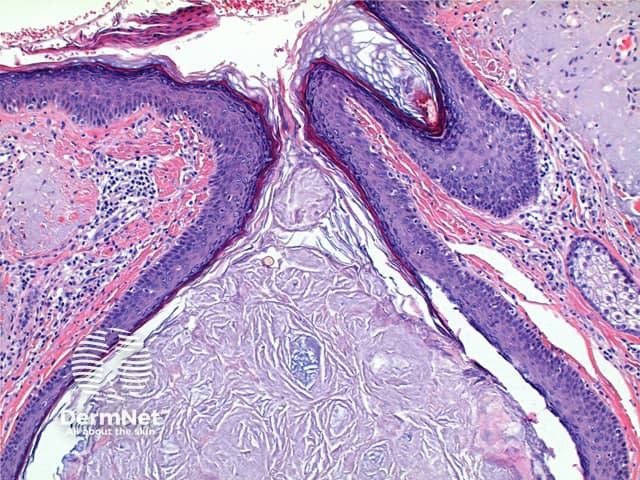

The low power view of Favre-Racouchot syndrome shows multiple comedones, dilated and plugged follicular infundibulae and epidermal cyst formation (Figures 1 and 2). This is set in a grossly solar damaged epidermis, which forms large nodules in the superficial dermis (Figure 3). The comedones are filled with compact keratinous material, while the epidermal cysts contain more loosely arranged laminated keratin (Figures 4 and 5).

Figure 2